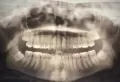

Была на приеме у одного стоматолога, сказал, что нужно удалять нижние восьмерки, одна из них - разрушена. Не больно постучали по нижней левой восьмерке, я выплюнула кусочки зуба. Пошла к другому стоматологу-хирургу, сделала панорамный снимок, сказал, что нужно удалять верхние восьмерки (сказал, что корни целые, но сами зубы - разрушены).

Скажите, пожалуйста, насколько это возможно, какие зубы нужно удалять?